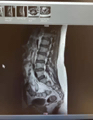

如题,患儿男,13岁,身高176,体重85㎏,行骶尾部核磁未见异常。